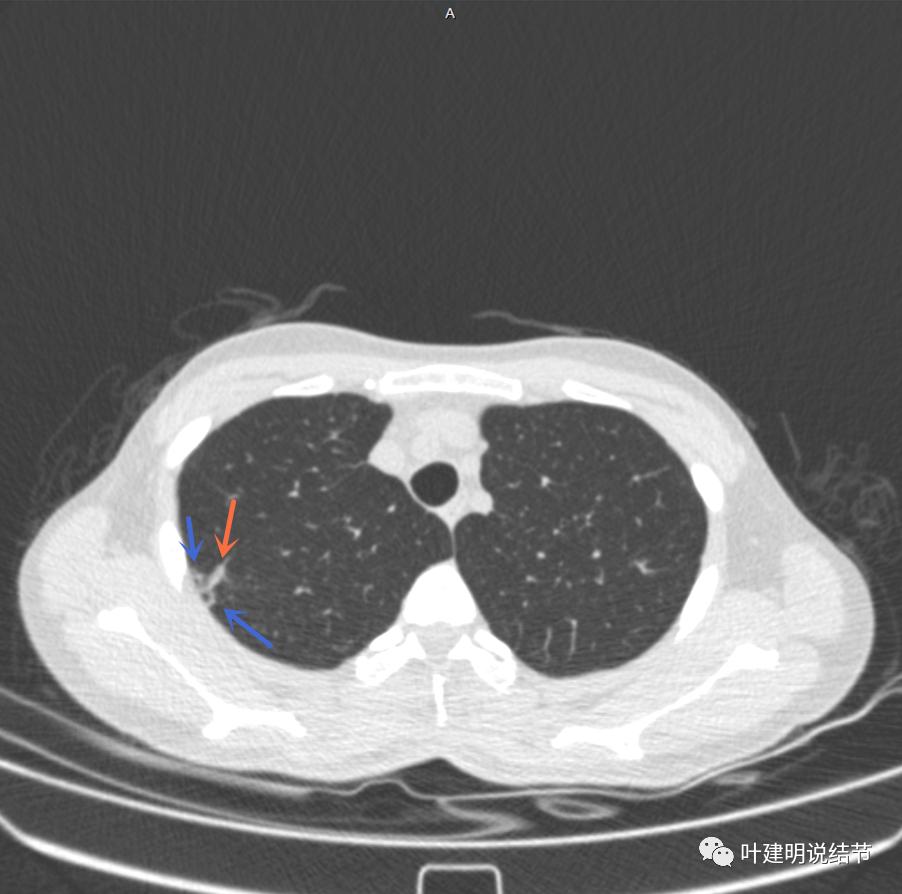

右肺尖偏实性结节(粉色箭头),邻近胸胸膜明显增厚不平,且广基附在胸壁上(蓝色箭头)

有卫星病灶(绿色箭头)

胸壁侧病灶较厚,模糊(蓝色箭头),仍见卫星灶(绿色箭头)